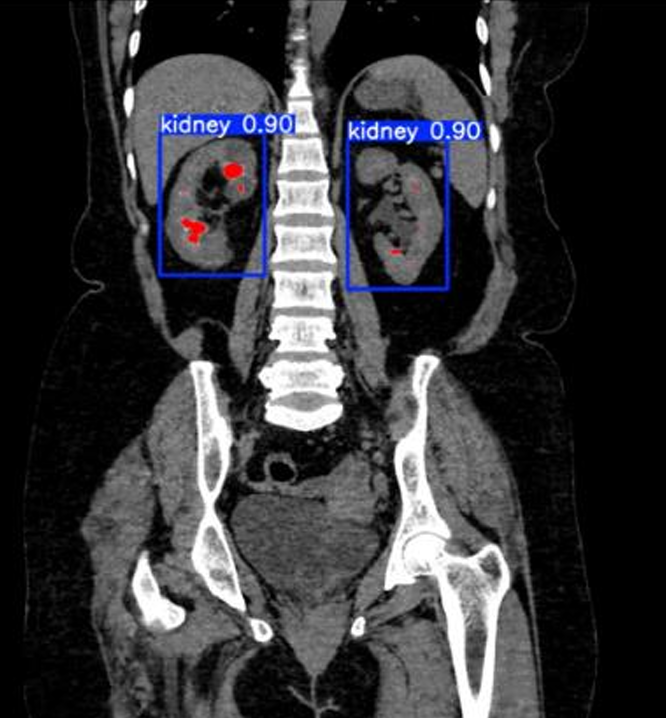

Automated Detection of Renal Calculi in Abdominal Computed Tomography Scans Using Deep Learning Techniques

La detección de cálculos renales en tomografías es clave para prevenir complicaciones y facilitar el tratamiento oportuno. Los métodos tradicionales requieren intervención manual, lo que puede ser laborioso y propenso a errores. Este estudio propone un sistema automatizado que integra:1) un clasificador MobileNetV2 para identificar la orientación del corte (axial/coronal); 2) un detector YOLOv8n que localiza los riñones con >95% de precisión; y 3) una segmentación adaptativa de los cálculos mediante umbralización de histograma. Se empleó un conjunto público con 2,757 imágenes abdominales CT. MobileNetV2 permitió clasificar automáticamente los planos, y YOLOv8 localizó los riñones eficientemente. El sistema logró 100% de sensibilidad, aunque con mayor tasa de falsos positivos, precisión de 75.76% y F1-Score de 84%. Estos resultados indican un alto potencial clínico, aunque se requieren mejoras para reducir falsos positivos y validar en más datos.